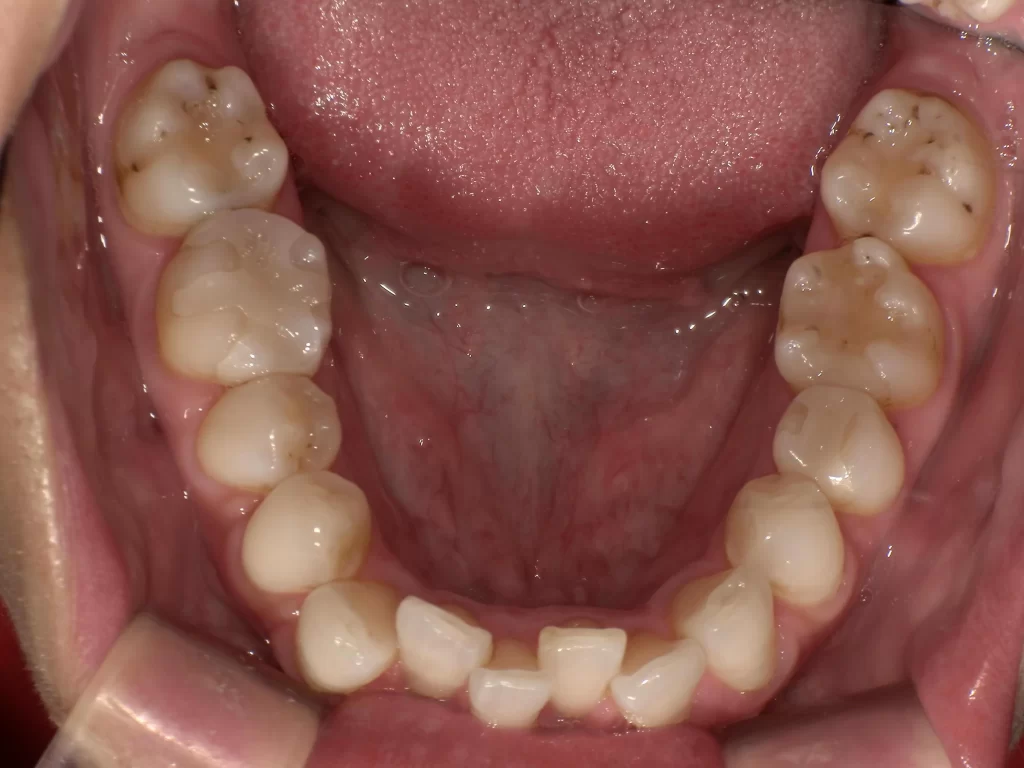

症例⑤:10歳・ガタガタ・出っ歯・深い噛み合わせ

【使用期間:3ヶ月】

歯が生えるスペースが足りずガタガタしており、噛み合わせも深い状態でした。

▼ 治療前(Before)

▼ 使用3ヶ月後(After)

- 年齢・症状: 10歳、叢生(ガタガタ)、過蓋咬合

- 治療法: プレオルソ

- 期間: 3ヶ月

- 結果: 装置を使うことで歯列の横幅が拡大し、ガタつきが自然に改善されました。深い噛み合わせも良くなっています。